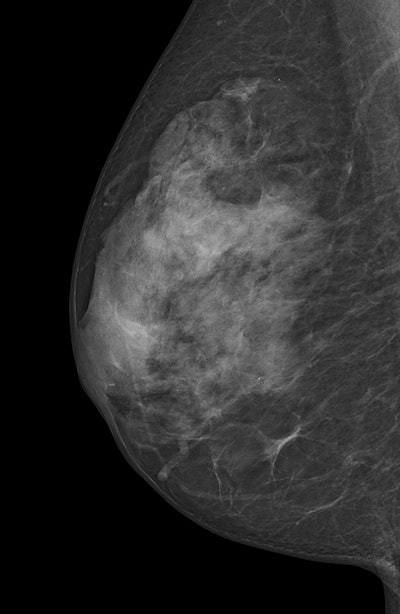

ACR's BI-RADS classifies breasts as almost entirely fatty (ACR 1), scattered areas of fibroglandular density (ACR 2), heterogeneously dense (ACR 3), or extremely dense (ACR 4). Heterogeneously dense and extremely dense are usually combined into one category of dense breasts. They are indicated by quartile ranges of percentage dense tissue more than 50% and as possibly obscuring small masses and lowering the sensitivity of mammography.

Most of the dense breasts are classified as heterogeneously dense and the frequency of breast densities is reported as 10% fatty, 40% scattered, 40% heterogeneously, and 10% extremely dense, the study authors explained. Higher breast density is associated with decreased mammographic sensitivity and specificity, as well as with increased breast cancer risk. Breast density may also be a factor that contributes differentially to screen-detected breast cancers and interval breast cancers, they added.